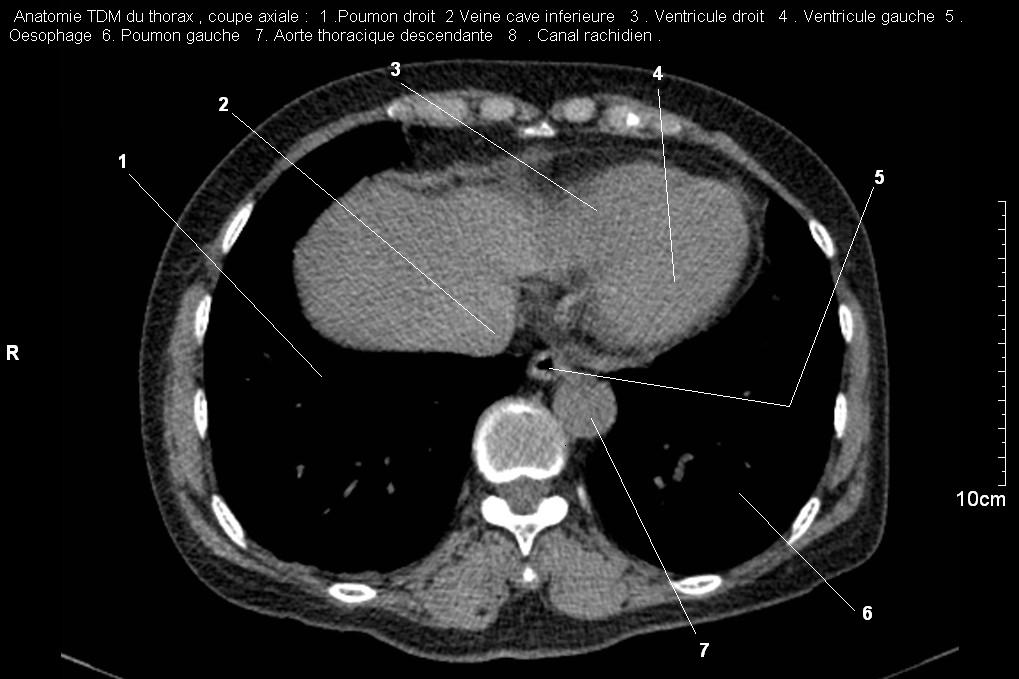

Au niveau du bronche souche

gauche ,oesophage se situe en arriere et avait

un peut serre .A gauche c'est aorte thoracique (

coupe axiale TDM thoracique au desous de bifurcation

tracheale ) . |

Coupe axiale TDM

thoracique au dessus de diapragme . Image si net de

oesophage situe en avant et a droite de aorte

thoracique . |